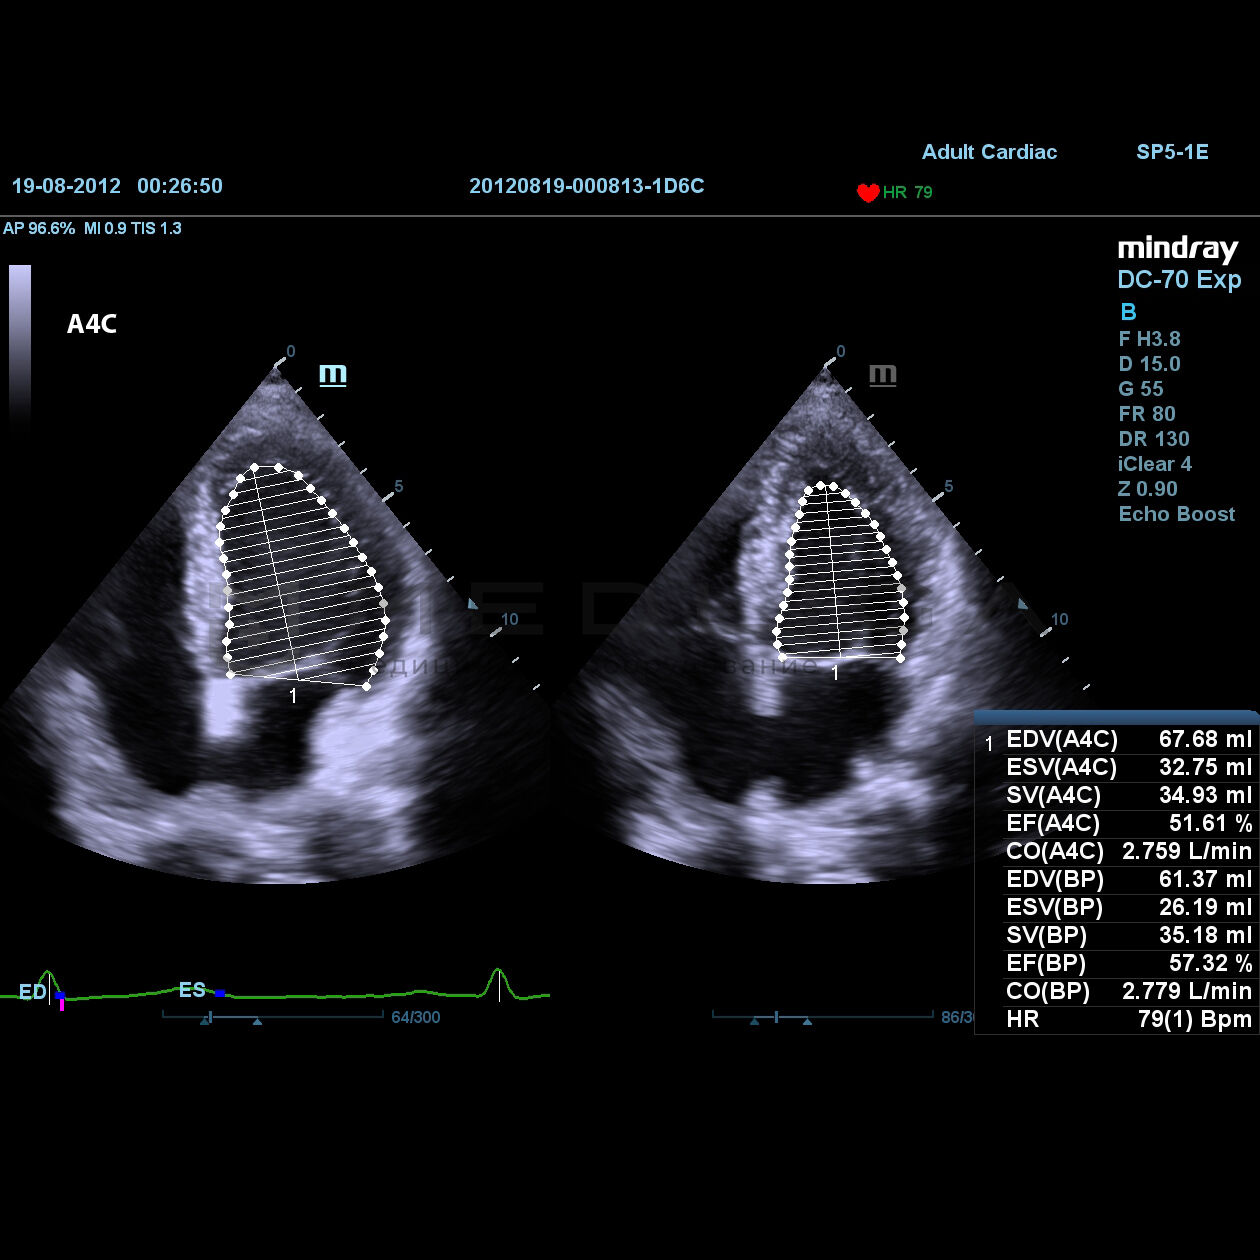

Auto EF

Auto EF - это интеллектуальный способ анализа изображений двухмерной эхокардиографии для автоматического распознавания диастолических и систолических кадров и вывода измерений для оценки функционирования таких параметров левого желудочка, как КДО, КСО и реакции выброса.

- Автоматическое распознавание А2C или А4С

- Автоматическое распознавание границы эндокарда

- Автоматическое распознавание диастолических и систолических значений